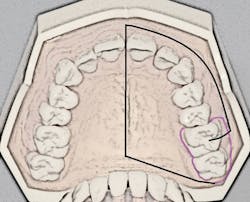

- Insertion site: The insertion site is located midportion of the anterior palate, approximately halfway along an imaginary line connecting the median palatal raphe (tissue overlying the palatal suture) and the palatal free gingival margin between the premolars1,3,4 (see Figure 2).